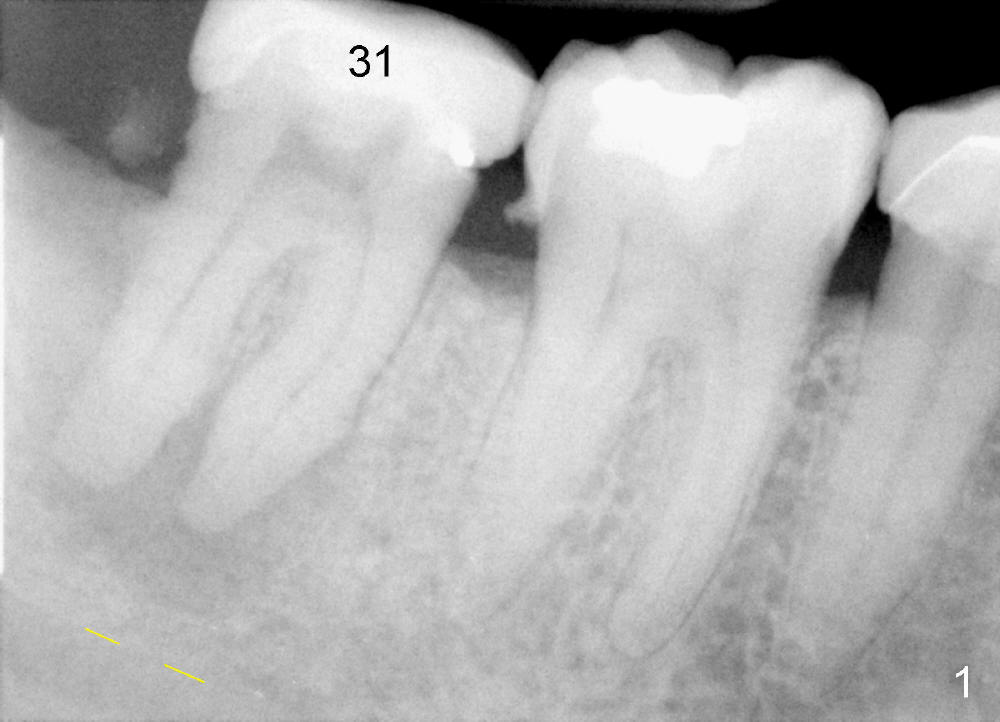

The gingiva forms a band (cuff) around the implant (Fig.11 *) and bone has apparently filled the peri-implant gap (Fig.13 *) 3.5 months postop. The gingival cuff is present immediately pre-crown cementation (Fig.12 *). The bone density around the implant continues to increase 2 and 7 months post cementation (Fig.14,15), in spite of retention of residual cement distally (<).